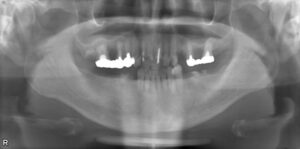

下顎臼歯2本欠損症例

BEFORE AFTER 63歳男性/下顎臼歯2本欠損/インプラント埋込手術 【治療内容】 下顎の大臼歯が左下第一大臼歯…